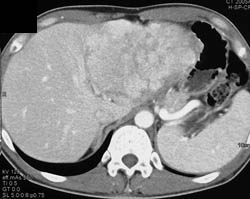

Diagnosis

Hepatoma